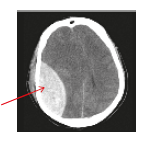

• Haematomas (Blood clots) refer to the collection of blood in one or several locations of the brain. Treatments for contusion and haematomas include observation for worsening of symptoms and removal of blood clots. Prognosis depends on the type, size, and eect of the injuries on the brain (Figure 3 and 4).

Bleeding from vein (Subdural haematoma)

Figure 4